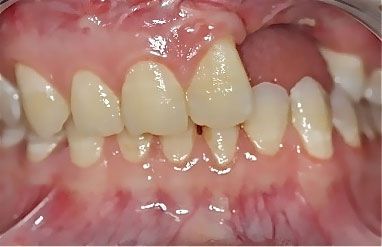

· высота линии улыбки (количество зубов и десны, видимых при жевании, речи и улыбке).

Фото. Высота линии улыбки. Чем выше у Вас линия улыбки, тем больше эстетический риск.